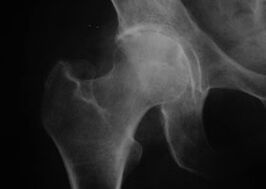

Coxatrose, Arthrose des Hüftgelenks

Röntgenaufnahme des Hüftgelenks mit Arthrose

Bei dieser Erkrankung wird ein klassisches Krankheitsbild der Arthrose beobachtet.

Das erste Symptom einer Coxarthrose sind Beschwerden im Hüftgelenk nach körperlicher Aktivität.

Bei fortschreitender Coxarthrose kommt es zu verstärkten Schmerzen, Steifheit und eingeschränkter Beweglichkeit.

Patienten, die an einer schweren Form der Coxarthrose leiden, schonen das betroffene Glied, vermeiden es, darauf zu treten und wählen im Stillstand Positionen, in denen die Schmerzen minimal sind.